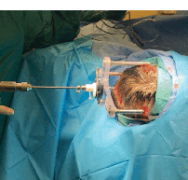

LITT激光间质热疗:针对医学难治性癫痫,目前各种手术技术都在突飞猛进。不同于传统的开颅手术,药物难治性癫痫的手术选择又有了新的“微创”之选——激光间质热疗LITT,该技术可...

打破难治性癫痫的治疗障碍:激光间质热疗LITT技术,有20%~30%的癫痫患者经过长期药物治疗仍不能控制发作,称为“药物难治性癫”,这部分患者中约30%可以通过癫痫外科手术而取得良...